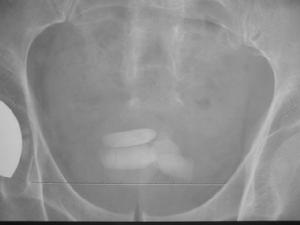

輸尿管結石輸尿管結石的正確診斷不僅是肯定有無結石,還要確定結石的大小、位置,兩側腎的功能和腎積水的程度,有無感染等。典型的腎絞痛與血尿是診斷的重要線索。在疼痛發作時肋脊區有壓痛、叩擊痛。女性輸尿管下端較大的結石能在陰道穹窿處觸及。 90%以上的輸尿管結石在尿路平片上可被顯示,草酸鈣顯示最佳,但需與腹腔淋巴結鈣化、盆腔內靜脈石、闌尾內糞石和骨島角相鑑別。靜脈尿路造影主要了解結石的部位和腎功能與有無積水,必要時行大劑量尿路造影及放射性核素腎圖>放射性核素腎圖檢查,均能進一步了解腎功能情況。膀胱鏡檢查與輸尿管插管在結石處受阻,並拍平片鈣化陰影在導管的同一平面,即能肯定輸尿管結石的診斷。陰性結石用空氣為對比劑作逆行造影攝片,則可顯示結石的存在。另外CT及B型超聲檢查有助於對X線平片不顯影結石的診斷。